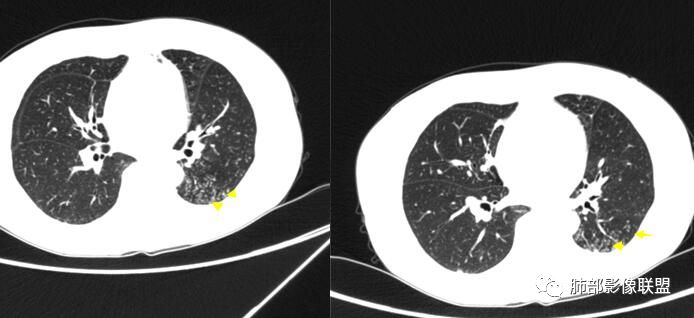

病灶远端有扩张支气管,树芽,实变,纵隔肺内淋巴结钙化,考虑肺结核。

下叶背段有树芽

左肺占位,边界平直,无明显膨胀性,炎性首先考虑,支气管壁不光滑,考虑气道来源,青年女性,有地热,乏力,体重减轻,结合病灶周围有树芽征,我考虑结核!

晨读:左肺上叶实变,边缘不整,部分膨隆,其内支气管有狭窄有扩张,周围小叶间隔增厚,左肺下叶背段可见气腔结节,树芽征,边缘模糊,肺门及纵膈淋巴结钙化,考虑结核。鉴别肺炎型肺癌。

1.双肺多发病灶,结节影、树丫影,边缘分布……病灶符合继发性肺结核。

2.左肺上叶大片实变影,密度不均,体积轻度增大,注意轻到中度强化及血管影未见破坏、未见坏死空洞……病灶更符合炎症,而不大支持干酪性结核及肺鳞癌等,后两者的破坏能力是比较强的。